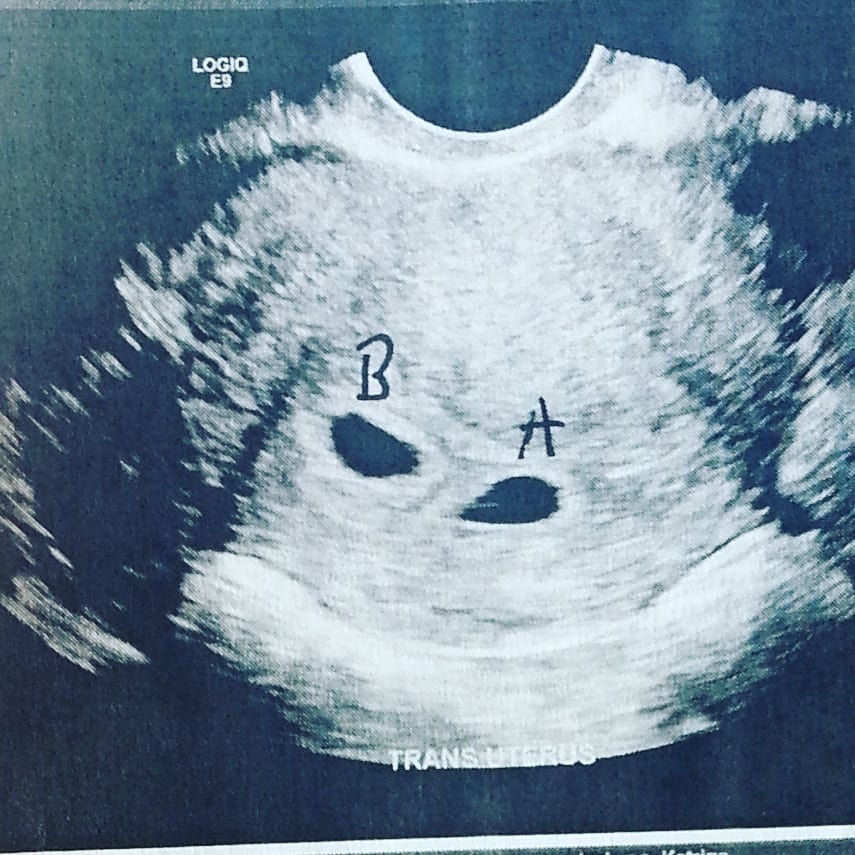

Ultrasound Photos – 8 Week Sonogram

8 week sonogra